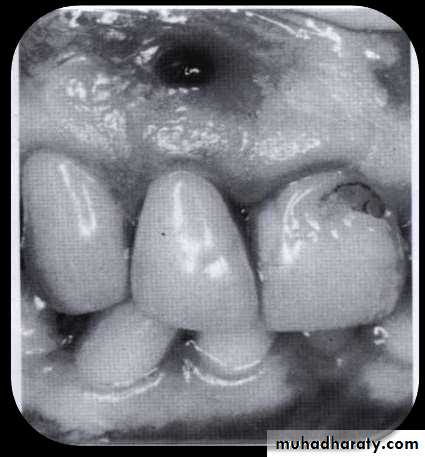

• Periodontal abscess

• A periodontal abscess is a localized accumulation of pus within the gingival wall of a periodontal pocket. Periodontal abscesses may be acute or chronic.• The acute periodontal abscess appears as an ovoid elevation of the gingiva along the lateral aspect of the root.

• The gingiva is edematous and red, with a smooth, shiny surface. The shape and consistency of the elevated area vary; the area may be domelike and relatively firm, or pointed and soft.

• In most cases, pus may be expressed from the gingival margin with gentle digital pressure.